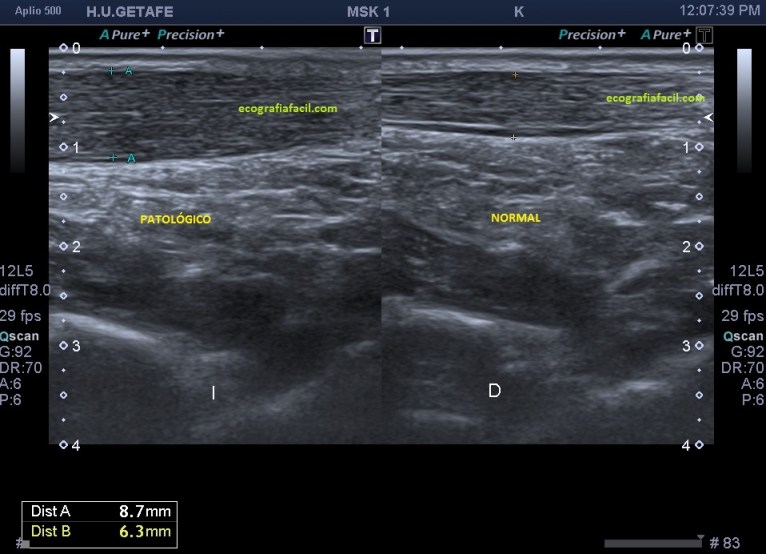

Lo más habitual es encontrar una tendinopatía del tendón, donde vamos a ver un tendón engrosado, hipoecogénico, normalmente a 5 cms de la inserción. Como puedes ver en la imagen 3. Vamos a ver varios grados en función de la afectación del tendón, puede ser global o afectar a fibras profundas o superficiales…siempre recurrir al estudio contralateral.

Ambas apariencias de las calcificaciones suelen verse acompañadas de tendinopatías, como muy puedes ver en la imagen 8 donde se demuestra un aumento del vientre del tendón marcado por la línea rosa, y como hemos dicho anteriormente, comos a unos 5 cms de la inserción.